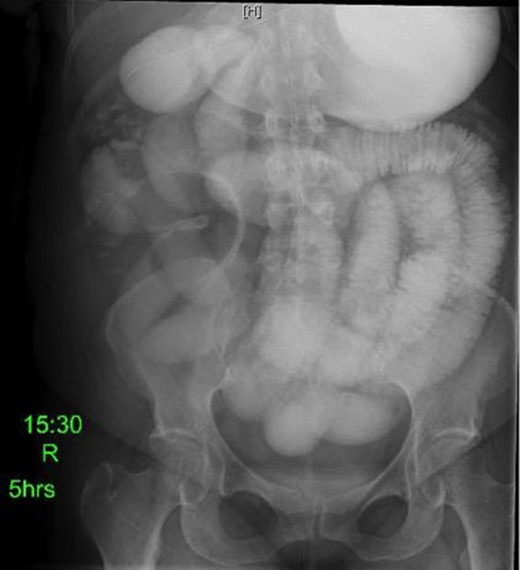

Laboratory studies were remarkable for leukocytosis, and an elevated lactate that improved with hydration (Fig. 1), while urinalysis was unremarkable. Abdominal CT scan obtained at this time demonstrated a partial SBO in the mid-small bowel as well as inflammation and thickening of the duodenum. A small bowel series was ordered, and showed high grade SBO (Figs 2–5).

Fluoroscopic barium study demonstrating oral contrast agent progression through the small bowel at 5 h after ingestion. Dilated bowel loops can be visualized throughout the abdomen, and transit time is delayed. Impression—high-grade distal small bowel obstruction.